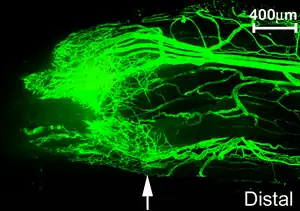

La microvasculatura o microvasos son aquellos vasos sanguíneos con un diámetro igual o menor a 100 micras y sus estructuras asociadas. La red microvascular se extiende dentro de los tejidos permitiendo que la sangre sea distribuida homogéneamente para realizar eficazmente su función. Este flujo sanguíneo se denomina microcirculación.

El desarrollo de un vaso sanguíneo es un proceso muy regulado, que involucra proliferación, migración y remodelación de células endoteliales de vasos preexistentes (angiogénesis), o producto de la diferenciación de las CPE o angioblastos procedentes de precursores mesodérmicos (vasculogénesis).[2]